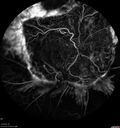

Proliferative diabetic retinopathy with vitreous hemorrhage181 views53 year old man with foggy vision in the left eye for one day. VA 20/25 OD, 20/40 OS. Diabetes for 10 years. Type IISep 16, 2023